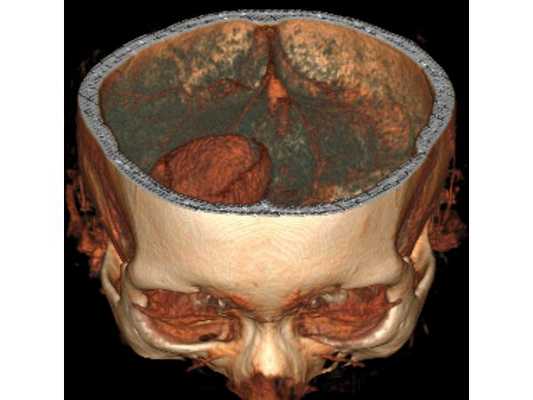

Интраоперационная фотография, выполненная после аспирации гнойного содержимого из полости абсцесса и промывания полости антисептическими растворами

На основании диагноза проведена краниотомия (трепанация черепа) и удаление абсцесса правой лобной доли: ⠀• выполнен дугообразный разрез мягких тканей в правой лобно-височной области; ⠀• наложено фрезевое отверстие у основания скулового отростка лобной кости, из которого краниотомом выпилен костный лоскут 6*5 см; ⠀• для остановки кровотечения использован хирургический воск и электрокоагуляция по ходу доступа; ⠀• произведено подковообразное вскрытие твёрдой мозговой оболочки основанием к сагиттальному синусу: абсцесс был хорошо отграничен капсулой и подпаянной к коре головного мозга твёрдой мозговой оболочкой; ⠀• тонким шпателем твёрдая мозговая оболочка постепенно отделена от коры, абсцесс вскрыт — получен гной, внешне напоминающий сливки, с гнилостным запахом; ⠀• аспирировано (удалено) около 60 мл гноя; ⠀• полость абсцесса многократно промыта водными растворами перекиси водорода и фурацилина, мозг запал, имеется хорошая пульсация; ⠀• твёрдая мозговая оболочка ушита, по периметру подшито трепанационное окно, костный лоскут уложен на место, на рану наложены послойные швы и асептическая повязка. При оперативных вмешательствах по поводу абсцесса головного мозга принято оставлять дренаж в полости абсцесса. Однако, с учётом наличия хорошо сформированной капсулы, которая была визуализирована после промывания полости антисептическими растворами, принято решение не оставлять дренаж.